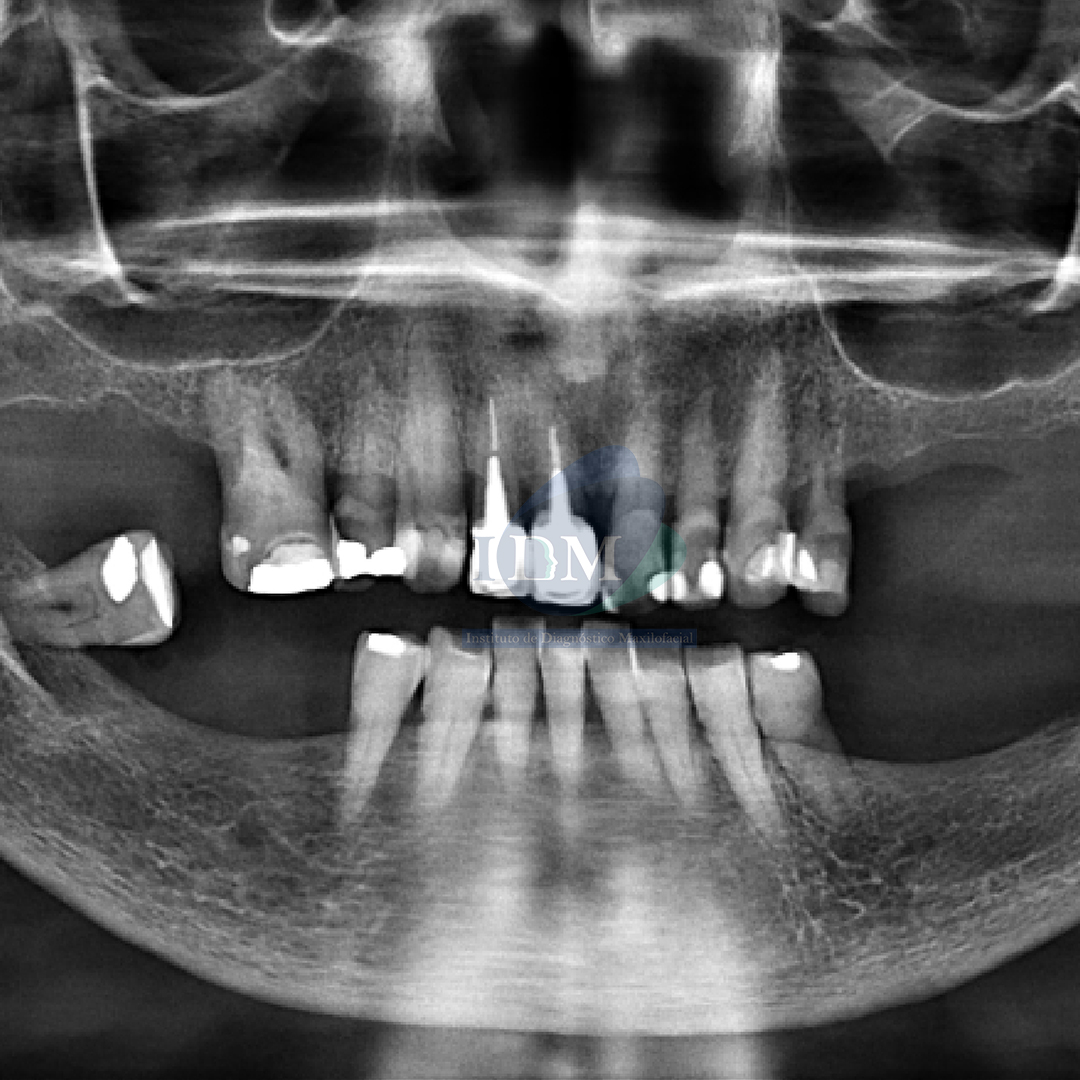

Paciente femenina de 72 años es referido al Instituto de Diagnostico Maxilofacial para una evaluación por imágenes sobre su estado de salud oral general.

Al observar la radiografía panorámica se aprecia, el aplanamiento del contorno condilar bilateral, la neumatización de ambos senos maxilares, edentulismo parcial de ambos maxilares, múltiples piezas dentarias con restauraciones coronarias. Piezas 12-11 con coronas protésicas, espigos intrarradiculares y obturación de conducto, asimismo se observa la reabsorción ósea del proceso alveolar.

Radiografia Panorámica